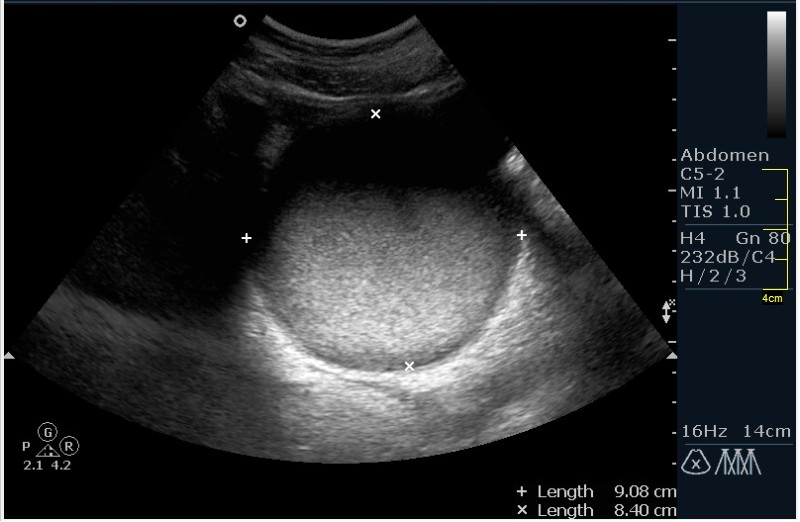

Девочка 12 лет; жалобы на частое мочеиспускание; тупые, тянущие боли в малом тазу. Менструацию отрицает. УЗИ малого таза, все сонограммы выполнены по средней линии, в поперечной и сагитальной проекциях.

Гематокольпос при заращении девственной плевы. Менархе. Врожденная аномалия половых органов.